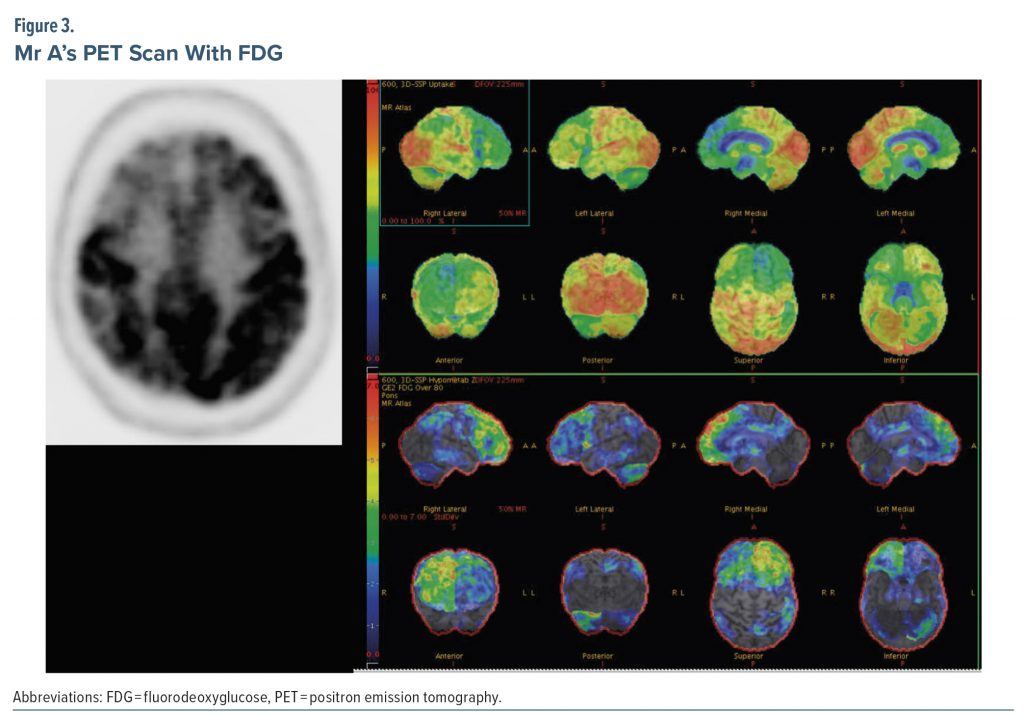

Due to the unclear etiology of dementia at this stage, the treating provider ordered a PET scan with FDG. FDG-PET can be useful in differentiating Alzheimer’s disease from frontotemporal dementia. Patterns of hypometabolism help distinguish between the 2 diagnoses, as well as between amnestic and nonamnestic Alzheimer’s disease (Murray et al, 2021). CT angiography head and fMRI brain are not indicated for routine evaluations of cognitive impairment.

Figure 3 shows results of the PET scan with FDG. The radiologist interpreted the study as demonstrating multiple areas of relatively decreased F-18 FDG labeling, indicating hypometabolism in the following areas: the convex surface of the frontal lobe bilaterally but more evident on the right side, the anterior cingulate cortices bilaterally, a small area of the most superior-posterior aspect of the convex surface of the right parietal lobe, and the anterior inferior aspect of the right temporal lobe in a patchy pattern. The rest of the brain cortical regions, basal ganglia, thalami, and cerebellar hemispheres were of a normal pattern comparatively. Due to involvement of the medial surfaces of the bilateral frontal lobes, convex surface of the right frontal lobe, bilateral anterior cingulate cortices, and right temporal lobe, the radiologist posited the findings to be most consistent with frontotemporal dementia. The radiologist further stated that Alzheimer’s dementia was unlikely given sparing of the left parietal cortex, major parts of the right parietal cortex, bilateral posterior cingulate cortices, and bilateral precuneus regions.